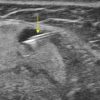

Hạch tuyến nước bọt

» Thông tin: Nữ giới – 66 tuổi.

» Lâm sàng: Sưng đau vùng góc hàm.

# Hạch lành tính ngoại vi tuyến nước bọt dưới hàm.